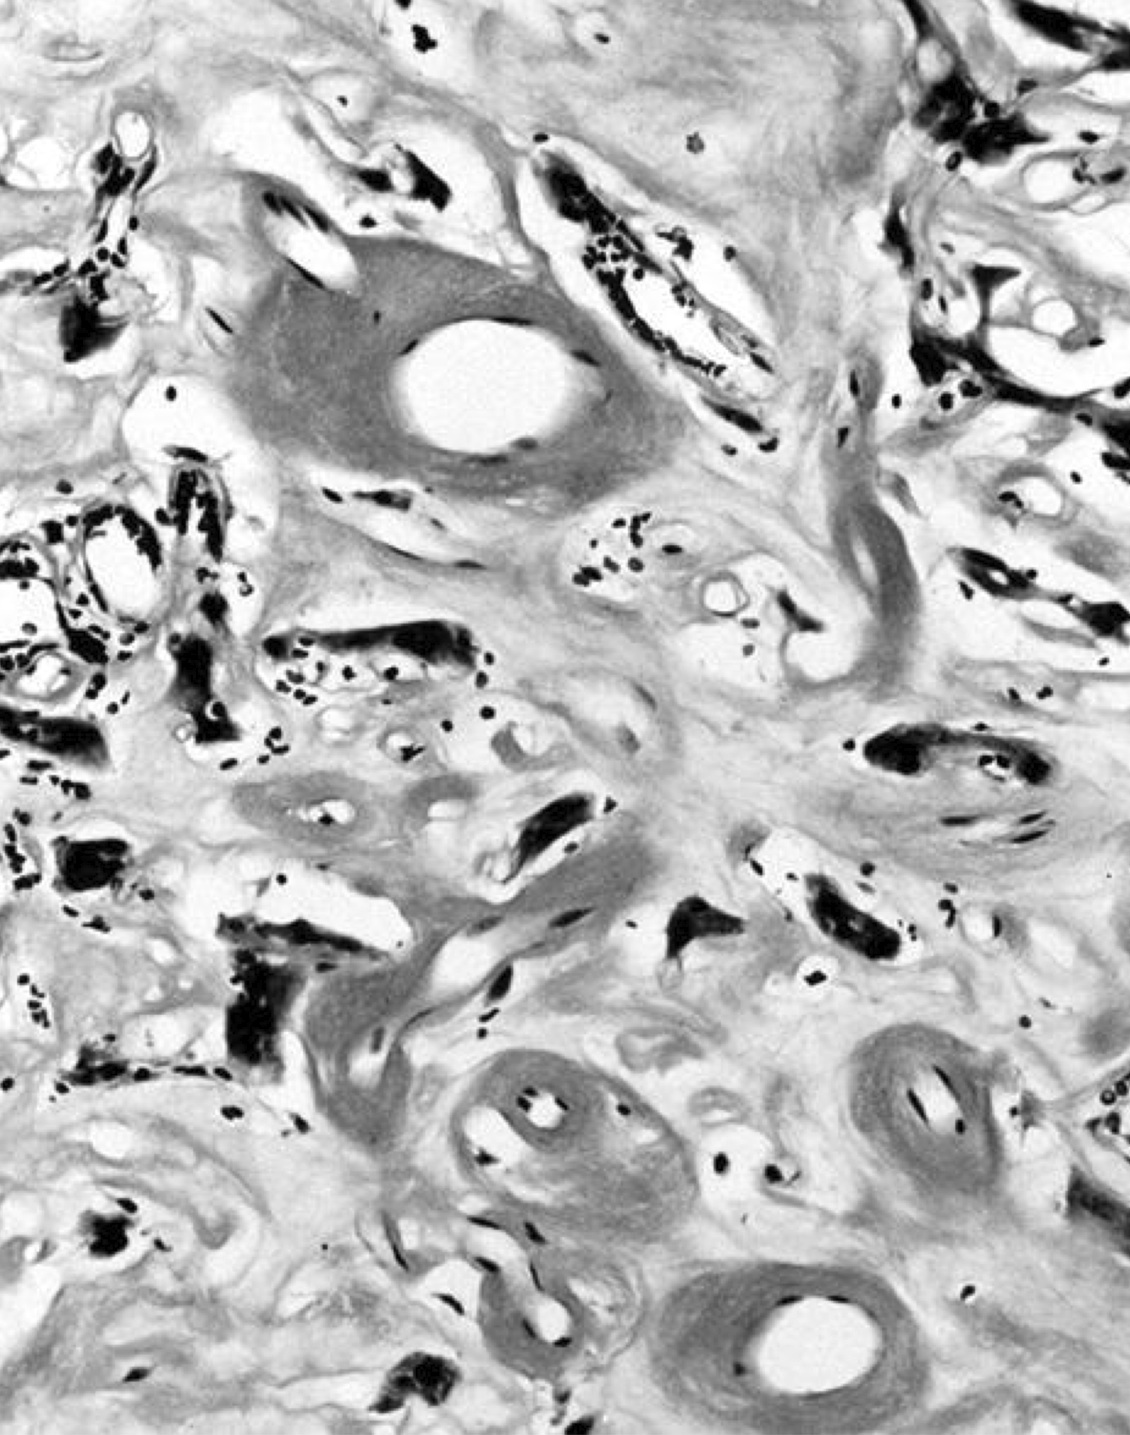

Microscopic (histologic) images

Contributed by Shipra Agarwal, M.D., Andrey Bychkov, M.D., Ph.D., Mark R. Wick, M.D., Asmaa Gaber Abdou, M.D. and AFIP

Not invasion:

- No capsular or vascular invasion after thorough sampling (at least 10 blocks)

- Minimally invasive follicular thyroid carcinoma:

- Thick capsule

- Vascular or capsular invasion

- May show increased mitotic activity; may have foci of necrosis